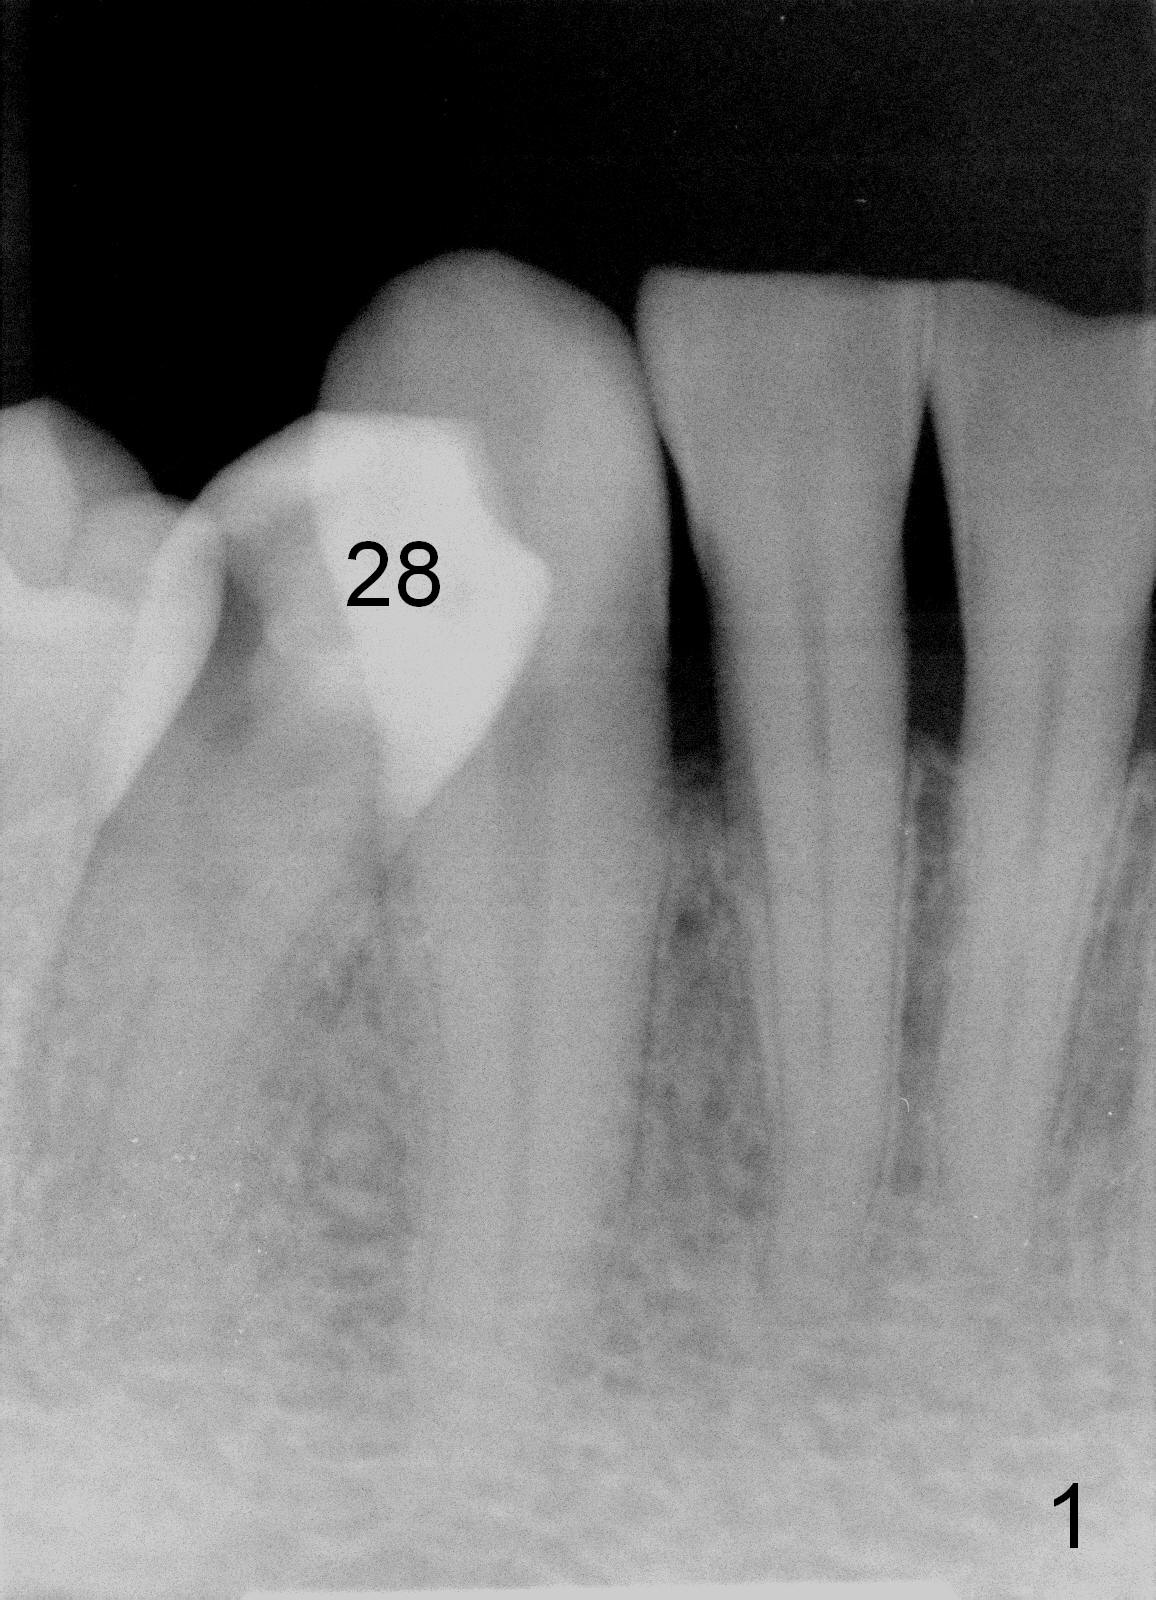

A 48-year-old man has Class I malocclusion associated with multiple treatment, including implants at #3 and 4 and RCT at #8 and 14 in this office.  A few years post composite restoration, the tooth #28 (linguoversion) develops acute pulpitis (Fig.1).  Initial RCT reveals profuse hemorrhage from the seemingly single and large canal, even after debridement with 40/.04 rotary file.  Ca(OH2) paste is placed and the patient is discharged.  Four weeks later, the tooth is still sensitive.  After local anesthesia, rubber dam is reloaded.  Assuming that the incomplete treatment is due to insufficient length, attempt to extend the canal debridement fails.  What should be done?